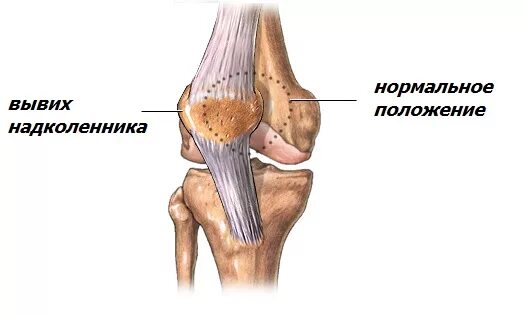

Вывих коленной чашечки у человека